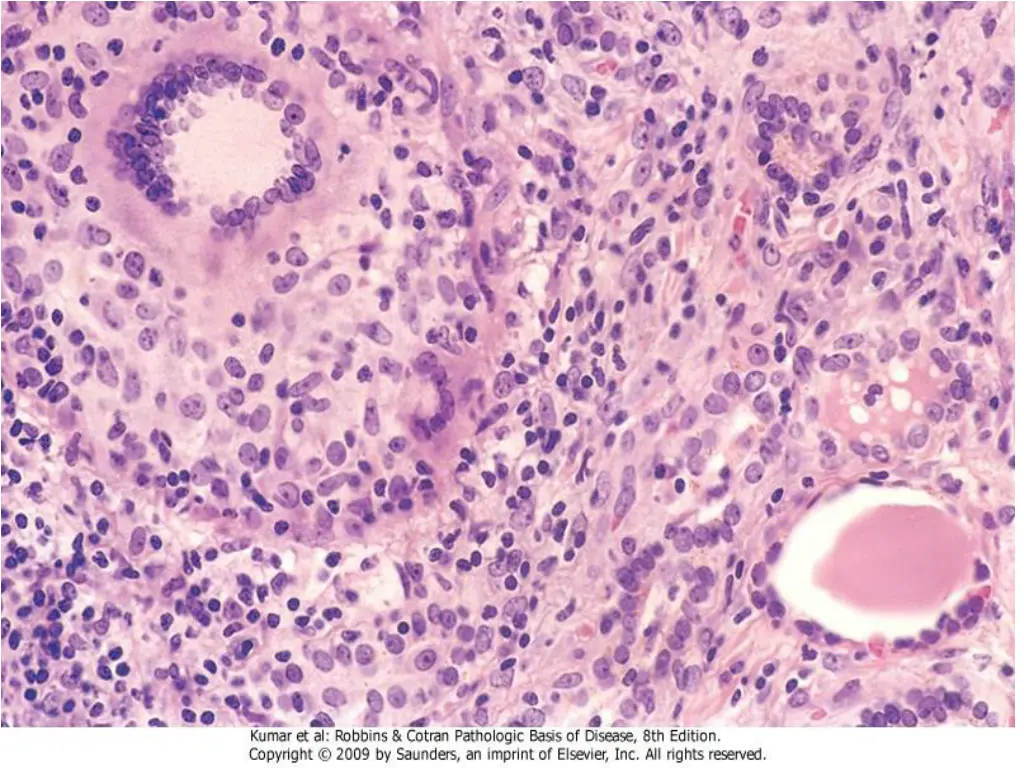

19. The thyroid is often diffusely enlarged The cut surface is pale, yellow, tan, firm and somewhat nodular. Microscopic examination reveals extensive infiltration of the parenchyma by a mononuclear inflammatory infiltrate containing small lymphocytes, plasma cells, and well-developed germinal centers The thyroid follicles are atrophic and are lined in many areas by epithelial cells distinguished by the presence of abundant eosinophilic, granular cytoplasm, termed H rthlecells.